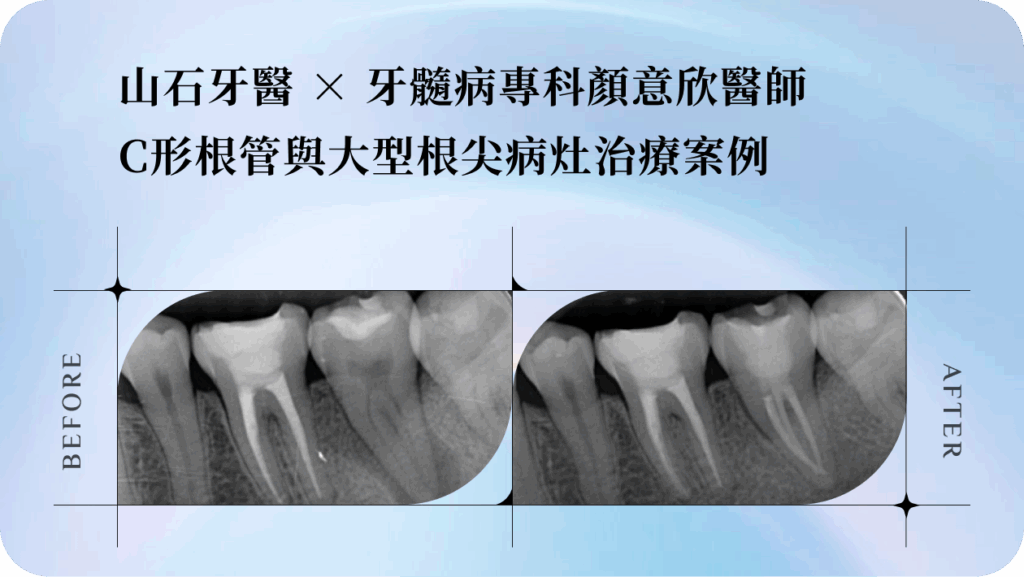

經 X 光與 CBCT 斷層影像評估後,牙髓病專科(根管專科)顏意欣醫師發現,這是一顆鈣化合併嚴重彎曲的根管。

這類狀況非常棘手——鈣化會封住根管開口、彎曲角度又大,若用傳統器械治療,極易發生器械斷裂或清潔不全。